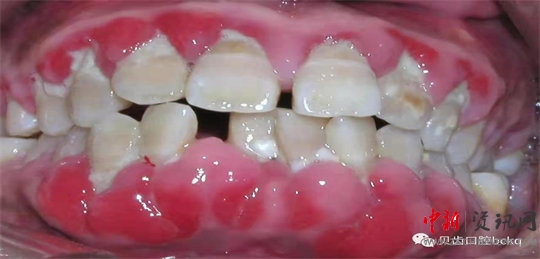

原來,在我們的牙根周圍,聚集著大量的細(xì)菌和食物殘屑。在某些特殊的情況下,這些污垢會(huì)形成結(jié)石,緊緊附著在我們的牙根周圍,并且越長(zhǎng)越深。結(jié)石是細(xì)菌生存的天堂,當(dāng)細(xì)菌接近到我們的牙槽骨的時(shí)候,就會(huì)造成骨頭的流失。此時(shí)的情景,就像大雨沖刷之下,樹根周圍的泥土逐漸被沖走,導(dǎo)致大樹傾倒是一樣的。